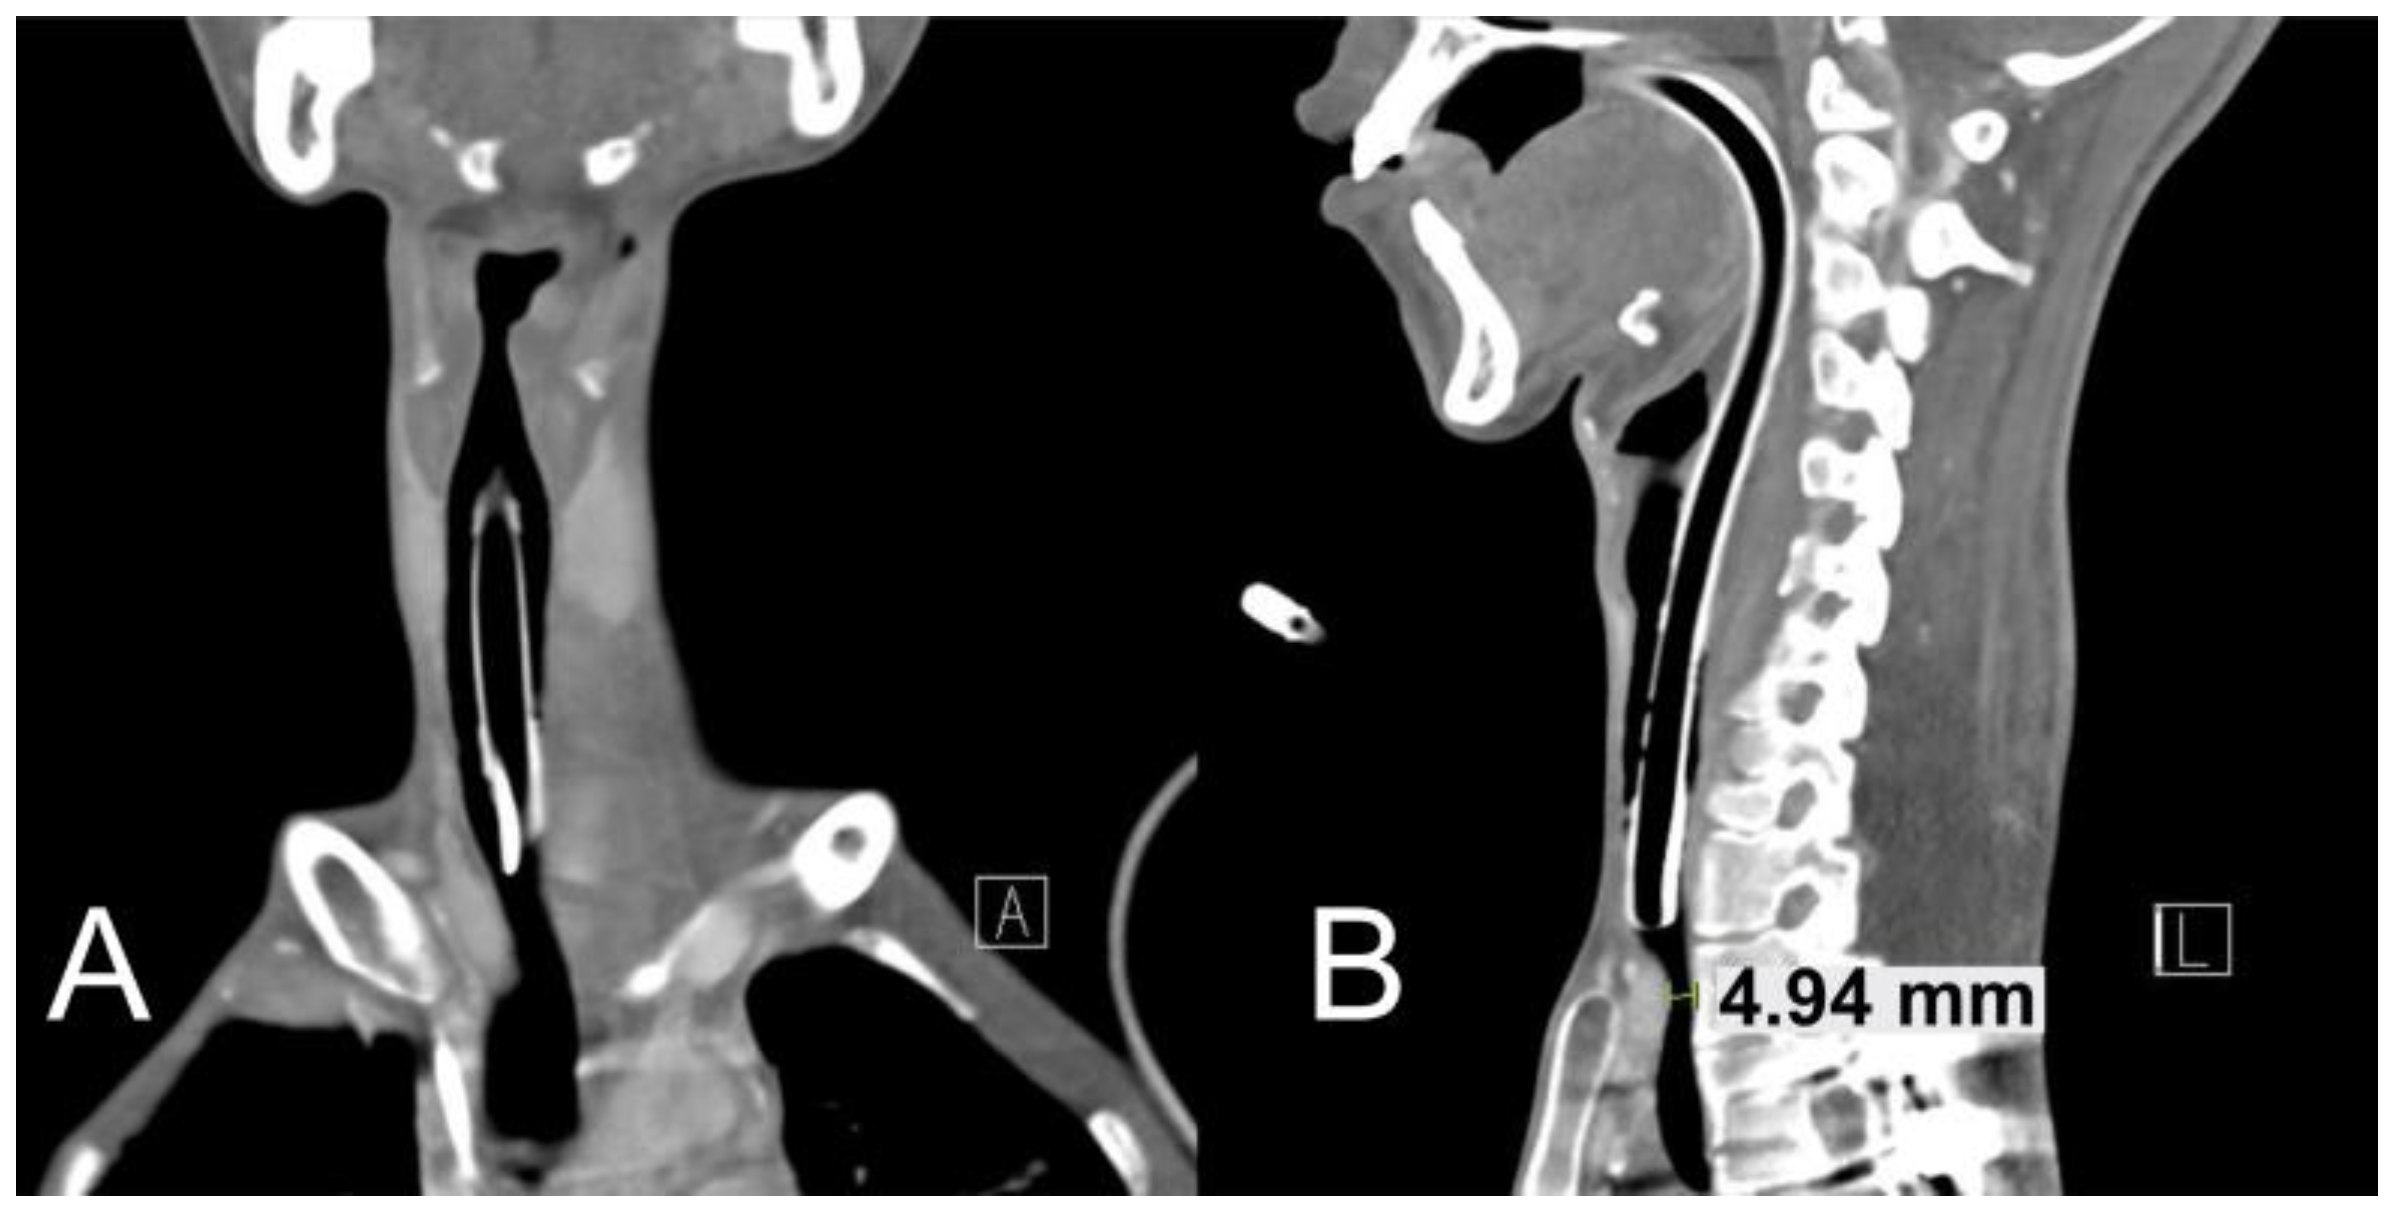

2.1. Case 1

2.2. Case 2